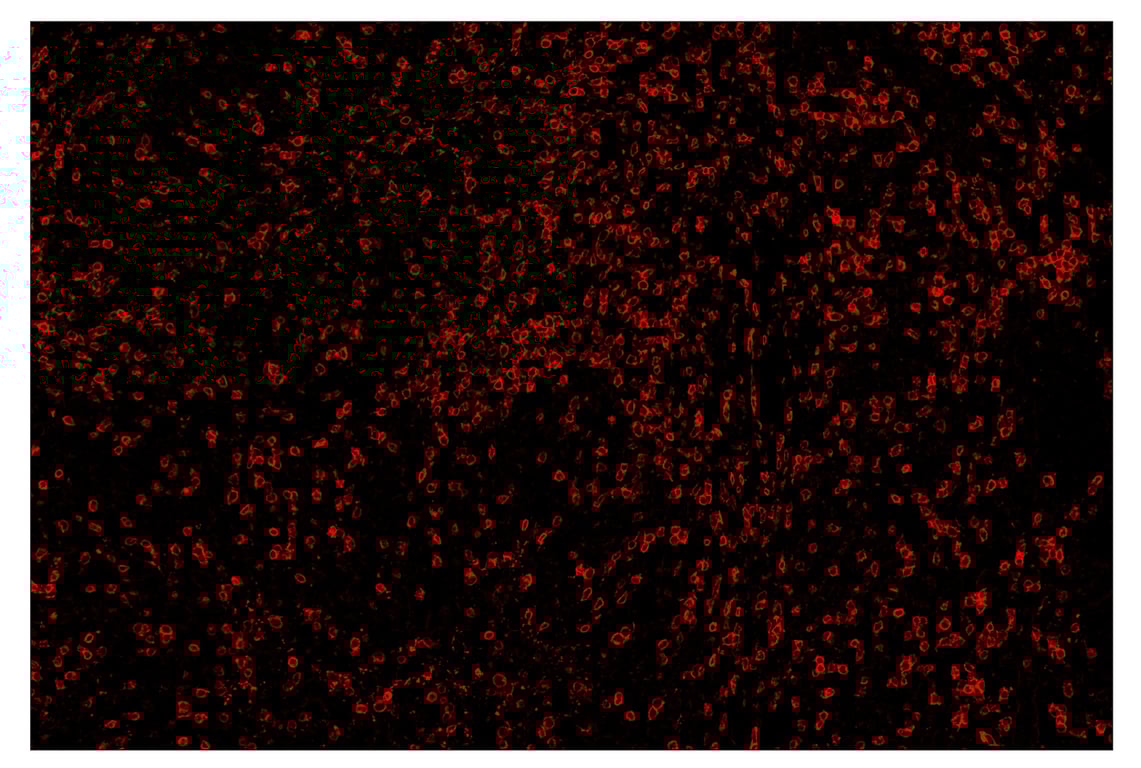

SignalStar™ immunohistochemical analysis of paraffin-embedded human gastric adenocarcinoma using CD3ε (D7A6E™) & CO-0001-647 SignalStar™ Oligo-Antibody Pair #33888 (red). All fluorophores have been assigned a pseudocolor, as indicated. Staining was performed on the Leica BOND Rx.

Immunohistochemistry Image 4: CD3 epsilon (D7A6E<sup>™</sup>) & CO-0001-750 SignalStar<sup>™</sup> Oligo-Antibody Pair